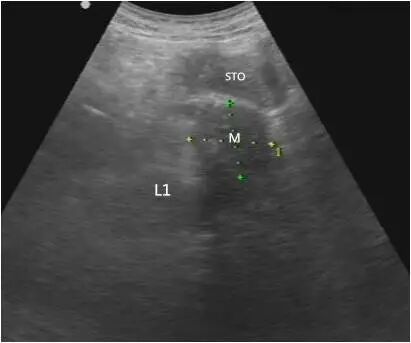

胰体尾部癌

第二种表现为胰腺内肿物不规则或有分叶状的团块回声,肿块边界不清,轮廓不整,向周围组织呈蟹足样或锯齿样浸润。

第三种表现为较小的肿块,内部大多数为均匀低回声,后方声衰减不明显;较大肿瘤呈混合回声,后方回声衰减,也可以看到坏死液化的无回声区。